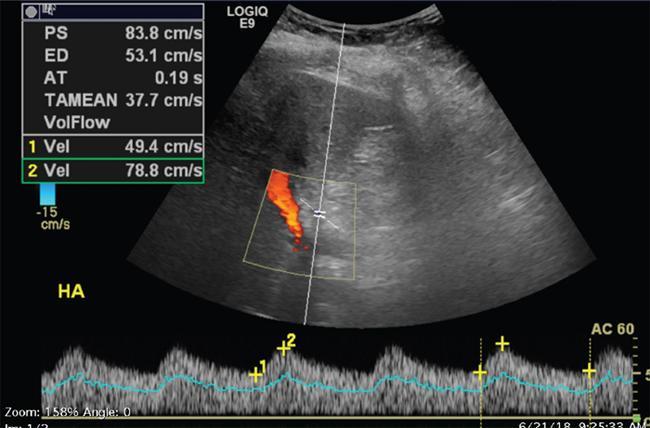

Imaging plays a significant role to make an early diagnosis and establish the best treatment options for posttransplant complications as clinical manifestations and laboratory parameters in many of the complications are usually nonspecific and overlapping. The imaging evaluation of postoperative complications remains the same in both types of liver transplants (DDLT and LDLT). Ultrasound with colour Doppler is usually the first modality of choice in the immediate postoperative period due to its easy and bed side availability with high accuracy and ability to pick up all major posttransplant complications, though it has a drawback of being operative dependent. It is usually part of regular postoperative assessment of the recipient for initial few postoperative days, playing an important role in picking up early complications. It is essential for the radiologist to know the details of the individual patient’s postoperative anatomy and surgical details, since anastomoses are the locations where complications occur most frequently. Goals of ultrasound evaluation in early postoperative period: Vascular evaluation with colour Doppler: CT/MRI imaging plays a supportive role for confirmation of the findings seen on ultrasound or colour Doppler or is done as an advanced imaging in case of mismatch between clinical or laboratory parameter and ultrasound or Doppler findings. MRI is particularly important for assessment of the biliary tree. First postoperative Doppler is done within 24 hours of the surgery and it serves as the baseline for comparison in the future. The haptic artery needs to be evaluated at the anastomotic site and also in the intrahepatic portions and the parameters to be evaluated are the systolic upstroke, PSV and resistive index (RI). Table 9.14.16 gives normal ranges of these parameters. Normal hepatic artery Doppler waveform demonstrates rapid systolic upstroke, with a systolic acceleration time (SAT) of less than 0.08 second and continuous diastolic flow, displayed above the baseline. A wide variability is observed in PSV of HA in the immediate postoperative period even in the absence of any hepatic arterial complication. Normal values may vary averagely from 40 to 120 cm/s. Vascular kinks or anastomotic site oedema in postoperative period can lead to falsely increased PSV in the HA. Correction of Doppler angle must be kept in mind while measuring the PSV of HA so that the angle aligns with the direction of the artery and must be less than 60 degrees to avoid inaccurate results. The hepatic arterial RI is an important tool to assess the hepatic arterial waveform in postliver transplant setting, as it allows semiquantitative estimation of the resistance to arterial flow into the liver. The normal RI ranges from 0.55 to 0.80 in posttransplant patients. The RI increases with decrease in the diastolic flow in the hepatic artery, which suggests increased resistance to the hepatic arterial flow. Absence or reversal of diastolic flow in the hepatic artery corresponds to an RI of 1.0 It is important to note that, increased RI of the hepatic artery (greater than 0.8) is a normal findings in the first few days after liver transplantation, due to decreased diastolic flow, which is attributed to allograft oedema, increased cold ischemia time, increased portal flow or vessel spasm. These transient arterial waveform abnormalities in early postoperative period usually resolve and normalize in 7–15 days on the follow-up Doppler studies. In view of significant variability in the PSV and RI of the hepatic artery in immediate postoperative period, other than in cases of absent arterial flow, the diagnosis of a hepatic arterial complication is seldom established on the basis of a single postoperative Doppler ultrasound. Arterial waveform abnormalities on the immediate postoperative scans should be followed closely and correlated with the patient’s clinical findings including liver function tests. Persistence of the abnormalities on serial follow-up Doppler studies or further deterioration of the waveform suggest presence of arterial complications. A decrease in hepatic arterial RI (RI < 0.55) is a more ominous finding than increased RI and is usually a concern for serious arterial complications like HA stenosis or impending thrombosis. The SAT – the interval from end-diastole to the first systolic peak – is a measure of the rapidity of the upstroke and normally should not exceed 0.08 seconds (Fig. 9.14.27). Portal vein evaluation needs to be done on greyscale ultrasound as well as on the colour Doppler. The presence of echogenic thrombus or filling defect is better appreciated on the greyscale ultrasound images. The PV peak velocity (measured at the anastomotic site) is the most important parameter for Doppler evaluation along with spectral waveform analysis. The normal portal vein flow after liver transplantation is hepatopetal, monophasic with respiratory plasticity (Fig. 9.14.28). The portal venous velocity is variable and tends to decrease on serial examinations after transplantation. During the early postoperative phase, turbulent flow with high velocities may be a normal finding which tend to decrease on serial examinations. Hepatic veins reveal a triphasic waveform (Fig. 9.14.29) due to transmission of cardiac pulsations. Though loss of triphasicity is seen in HV stenosis, it is a very nonspecific finding and biphasic or monophasic waveforms are often seen in normal posttransplant patients. Therefore, presence of hepatic venous triphasicity can exclude hepatic venous stenosis; however, loss of triphasicity does not imply presence of a hepatic venous complication. The terms early posttransplant complications is variably used in literature for period of first 1–3 months after the OLT. Table 9.14.17 summarizes post transplant complications in early and late post transplant period. Vascular complications are a common cause for allograft failure after hepatic transplantation. Early detection of the vascular complications is possible with the help of imaging, which can help reduce the incidence of graft failure. Table 9.14.18 below describes approximate timeline of various post transplant complications in post transplant period. Hepatic artery stenosis First three months Portal venous thrombosis Majority within four weeks Portal vein stenosis Usually late (>6 months) Hepatic venous stenosis Usually late (>6 months) Hepatic arterial complications are particularly significant in postliver transplant patients, as unlike native liver, the biliary tree of a transplant liver is entirely dependent on arterial blood from the hepatic artery. As a consequence, any hepatic arterial complication resulting in compromised hepatic arterial flow, particularly hepatic arterial thrombosis, has a devastating effect on the biliary epithelium, inducing ischemia resulting in biliary strictures, necrosis, abscesses and allograft failure. Hepatic artery complications include HAT, stenosis, and pseudoaneurysms. HAT is a common and the most catastrophic complication after orthotopic liver transplant, and it represents more than 50% of all arterial complications. According to the onset, HAT can be defined as early (within the first month) or late (later than one month). The incidence of early HAT is approximately 4%–12% in adults and 42% in children, and it is a major cause of graft loss (53.1%) and mortality (33.3%) in the early postoperative period. Thrombosis occurring after the first month or late HAT has a more insidious clinical course and is less devastating. Other than surgical technical causes like small calibre vessels or size discrepancy in the donor and recipient vessels, stenotic anastomosis, kinking; several nonsurgical causes have been described for HAT, which include ABO blood type incompatibility, increased cold ischemic time of the donor liver, acute rejection and sluggish flow through the hepatic artery. Initially, symptoms, signs and abnormal laboratory values are absent in early HAT, whereas reduced or absence of flow within the hepatic artery can be readily picked up by bedside Ultrasound and Colour Doppler evaluation (Table 9.14.19). Ultrasound is diagnostic in 92% of cases of HAT. Timely diagnosis of HAT allows for therapeutic interventions to restore the hepatic artery patency by vascular intervention or surgical reexploration to salvage the graft; if these measures fail retransplantation is needed in most cases. On Doppler ultrasound, acute HAT is diagnosed by: Graft oedema, systemic hypotension, and high-grade hepatic artery stenosis (HAS) can lead to false-positive sonographic diagnosis of HAT; whereas, false-negative sonographic findings may occur in presence of periportal arterial collateral formation in chronic thrombosis. CT or MRI with standard angiographic protocol are usually performed to confirm the diagnosis, which will reveal a complete cut off of the hepatic artery after the anastomosis (Fig. 9.14.30). Arterial anatomical variations like replaced recipient hepatic artery or any technical modifications used during arterial anastomosis need to be noted while reporting the angiography, which can guide the interventional radiologist in a better way. In late stages of HAT, hepatic arterial collaterals can develop. This collateral vessel flow can cause a dampened (tardus parvus) hepatic arterial waveform with a prolonged acceleration time (AT), similar to that seen in significant HAS. Presence of tardus parvus waveforms in the distal hepatic arteries is an ominous sign and must not be considered evidence of patency of the hepatic artery; it rather indicates the presence of either proximal stenosis or thrombosis. HAS has reported incidence of 5%–11% in posttransplant patients and is the second most common postliver transplant vascular complication. It usually occurs within 3 months of transplantation and most commonly involves the site of anastomosis. Risk factors for HAS are similar to those for HAT with few additional causes including clamp injury and intimal trauma from a perfusion catheter. If left untreated or undiagnosed, it can progress to HAT (Fig. 9.14.32) and related complications including hepatic ischemia, biliary complications, sepsis and ultimately graft loss. Treatment options aim at reestablishing adequate blood flow at the earliest either with angiographic intervention involving balloon angioplasty or stenting or with surgery if the previous measures are unsuccessful.